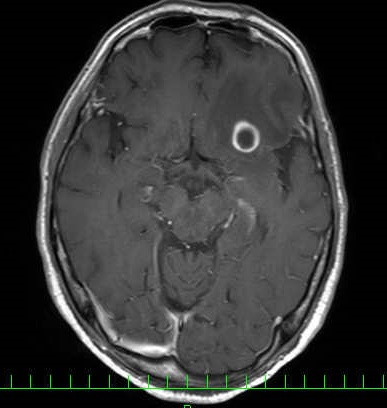

頭部造影MRI検査画像(肺がん脳転移)